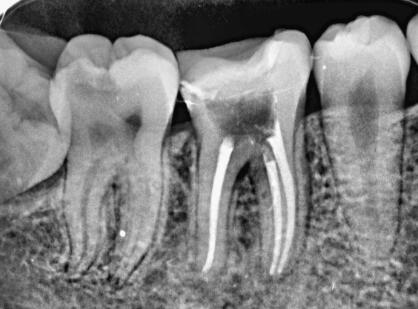

根据一些调查,在东莞根管医治的费用大约是400元起,由于一些原因会导致价格不一样,比方说会因为医治的次数不同和所用材料好坏等因素导致价格不同,至于浮动的具体原因解释如下:

1、医治的次数影响价格。有些根管病例相对简单,一两次就能完成。但更多情况下,由于牙友自身的口腔状况或疾病严重程度,医治可能需要多次复诊,甚至是反复修复和观察。而每一次复诊都需要消耗诊疗时间、耗材和医生的专业劳动。对于一些疑难杂症,医治过程往往异常曲折,医生付出的时间和精力成倍增加。医院为了合理收费,自然会将这部分成本计入总费用之中。

2、材料的好坏影响价格。材料的品质直接影响了根管医治的成功概率。比方说进口的的根管医治材料往往具有更好的生物相容性、抗渗透性和封闭性,能够预防根尖周炎等并发症的发生。而且,高品质的材料具有更高的弹性和耐用性,在制备根管时不易发生断裂。相比之下,低劣的材料可能会影响根管医治的预后,增加并发症发生的风险,带来额外的成本。